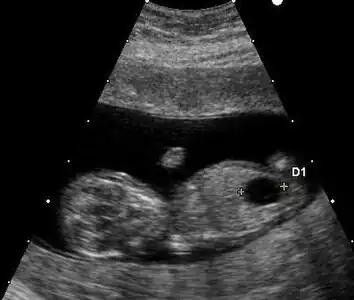

Ultrasound

Prenatal ultrasound can be used to screen for Down syndrome. Findings that indicate increased chances when seen at 14 to 24 weeks of gestation include a small or no nasal bone, large ventricles, nuchal fold thickness, and an abnormal right subclavian artery, among others.[113] The presence or absence of many markers is more accurate.[113] Increased fetal nuchal translucency (NT) indicates an increased possibility of Down syndrome picking up 75–80% of cases and being falsely positive in 6%.[114]

Enlarged NT and absent nasal bone in a fetus at 11 weeks with Down syndrome